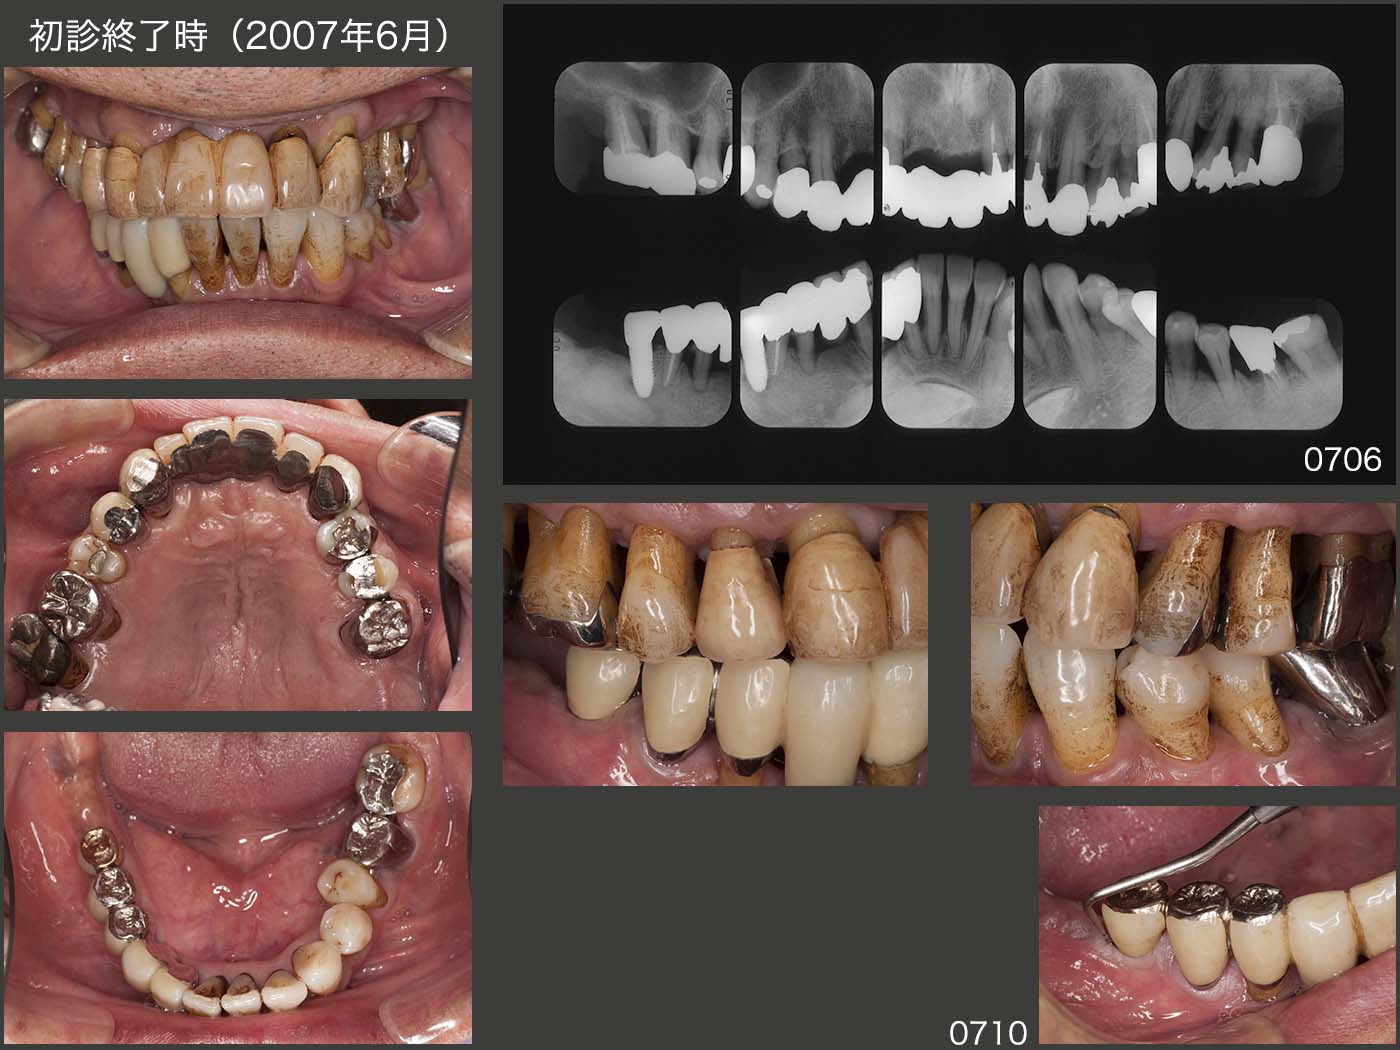

2007年6月,右側の咬合支持を確保したところで初診終了となった.アップライトした左下5を隣在歯と固定するか迷ったが,今回は固定せず経過をみることにした.喫煙の習慣があり,歯周ポケットも存在することから決して予断が許されない症例であると認識していた.

07年10月,1回目のリコール時に右下のインプラントのポケットが10mmの値を示し,唖然とした.しかし,ここでいきなり再治療とはいかず,患者さんによく説明し,経過をみることになった.